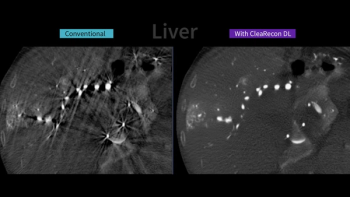

The CleaRecon DL software reportedly removes streak artifacts that can occur with the use of cone-beam computed tomography (CBCT) during interventional radiology procedures.